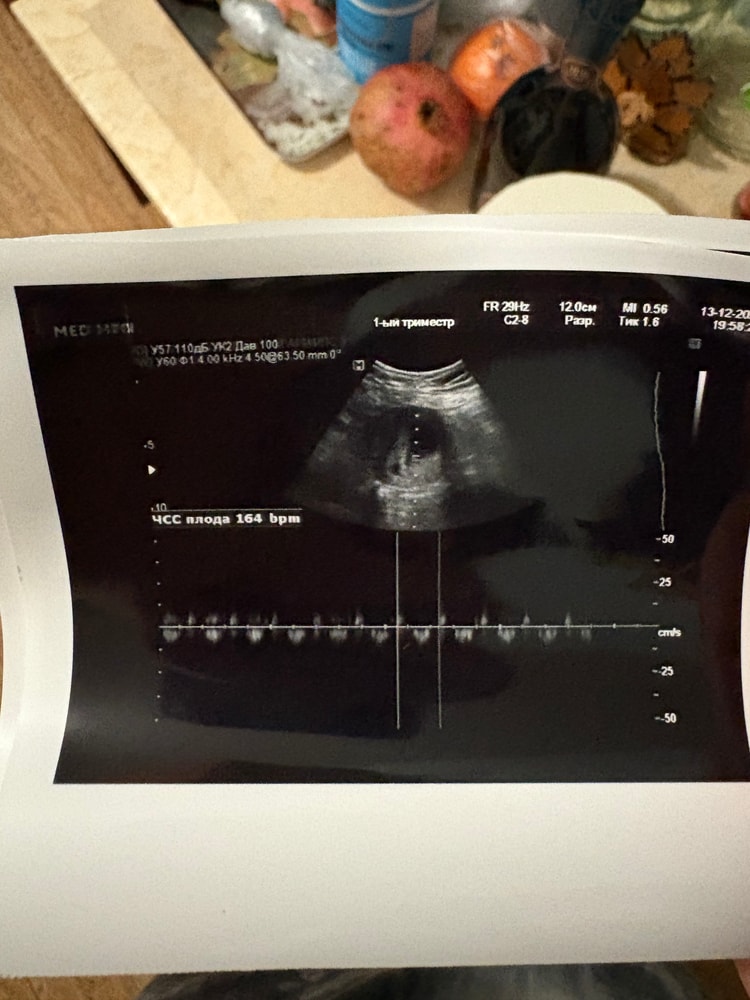

Болит живот и поясница, тонус, треникиДевочки, сос. Сейчас увидела у себя выделения какие-то неважнецкие. Персиковые, розовые. Не знаю как объяснить. Время позднее, побежала на узи, какое было. Сказали, что с малышом все хорошо. У меня по месячным срок 7,6. Там смотрели абдоминально. Прям для меня картинка была расплывчатая. Намерили ктр на срок 6,5. У меня такой ктр был неделю назад. Я запереживала. Потом увидели гематому, сказали маленькая гематомка выходит, плацента прикреплена по задней стенке внизу, может из-за этого. Отпустили, сказали, что все нормально. А я переживаю. Прикреплю фото. Гематому видно слева от плодного яйца. Я еще не успела встать на учет. К врачу еще не знаю когда обращусь. В прошлую беременность лежала на сохранении с гематомой. Врач говорила утражестан ставить. А перед выпиской кажется дюфастон или что-то такое. Кто тоже с таким сталкивался? Без крови, но увидели гематому. Какой прогестерон назначали? Что посоветуете. Понимаю, что нельзя заниматься самодеятельностью. Но в связи с тем, что вообще не могу обратиться к врачу экстренно, плюс крови нет, ложиться на сохранения пока не вижу смысла. Думаю, что врач так и так прогестерон пропишет.